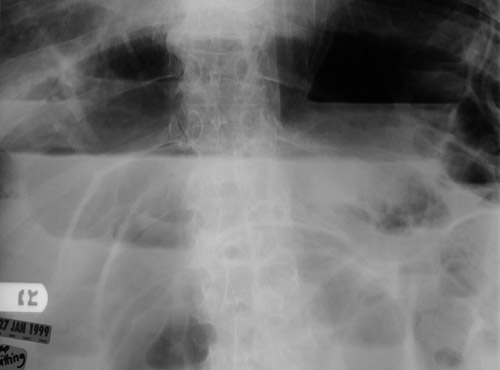

![]() | This abdominal radiograph demonstrates many loops of small bowel dilated with air as a consequence of bowel obstruction from cecal volvulus. In the magnified view below, air-fluid layering is present in the loops of bowel as a consequence of the ileus (lack of peristalsis). |